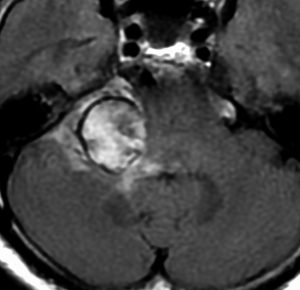

この腫瘍は脳幹部変形がとても強く,大きいので手術摘出するしか選択肢はありません

- 脳幹部の変形が高度な大きな腫瘍になると手術するしかありません

- 4cmを超えると危険だと考えてください

- のう胞性(腫瘍の内部がほとんど液体)のものは4cmを超えても手術は危なくないです

- 巨大な充実性の聴神経腫瘍の手術では命をなくすリスクもあるものです

聴神経腫瘍でまず手術が必要なのは巨大なものです。この4枚の写真は私が実際に手術をした患者さんのものです。脳幹部という脳の最も大切なところが腫瘍によって圧迫されて変形しているのが特徴です。右上のものはのう胞性腫瘍なので大きさの割に手術のリスクは高くありませんが,左上のものは実質性で出血性のものですごくリスクが高い手術でした。左下のものは普通のリスク。右下のものは超高難易度のものです。